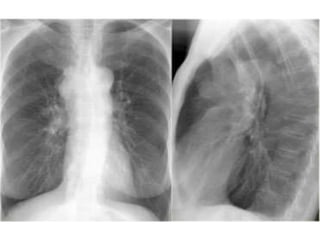

bronchi are not separately visualised

 But when, there is opacification of the alveoli due

to various reasons (eg: fluid accumulation is

pulmonary oedema)the bronchi stand out as

radiolucent in contrast to the adjacent alveoli

that are radio opaque

an x-ray for a patient with right middle

zone consolidation and demonstrates

air bronchograms